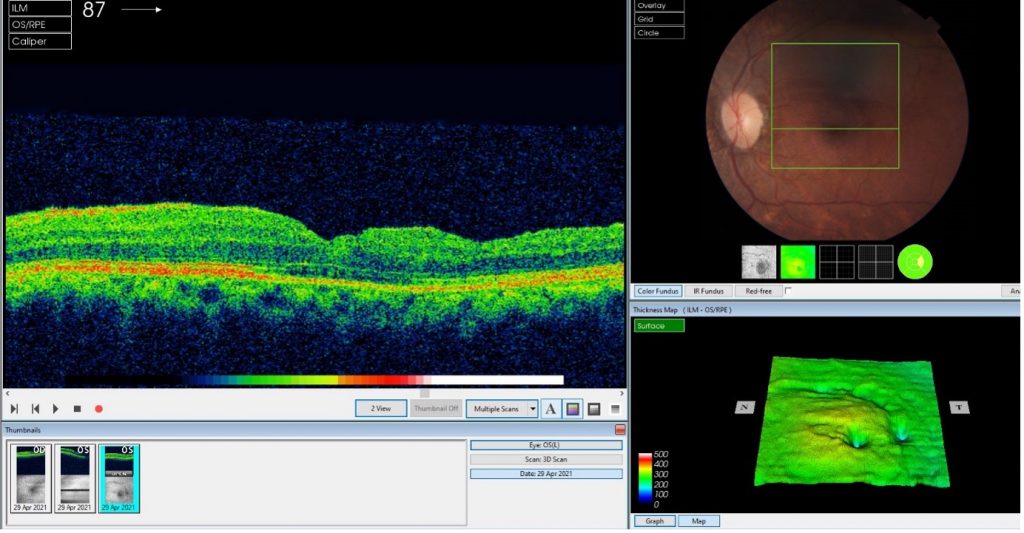

Macular hole pre-surgical repair

Macular hole post-surgical repair